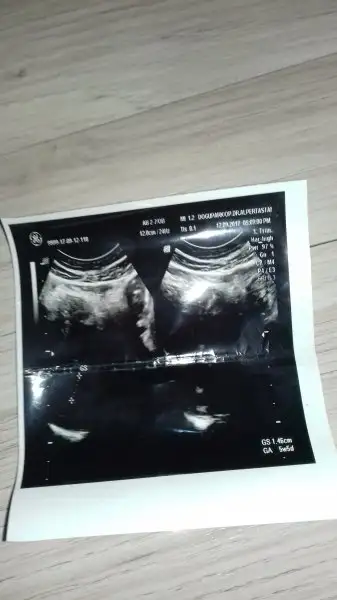

Cnm ben de dosya yükle dediğimde hiç birşey olmuyor telefondan kaynaklı galiba senden değil. Maşallah bebişe nazar değmesin.Bi foto yükleyemedim allah beni napmasın.. Kızlar normalde 8 haftalık olması gerekiyormuş ama 5 haftalıkmış yumurtlama geç oluşmuş dedi Dr birde kese görünüyor ama bebek görünmüyor dedi 1 hafta sonra gelip kalp atışını dinleyebilürsün dedi.. 1.46 cm minnacık yaaaaa

Cnm bnce var haftaya gidince kalp atışiyla gorursun bebişini sadece bebek küçük ondan dir boşuna stres yapma üzme kendinikızlar sizlerede sormak istiyorum az önce nette bişey okudum moralim çok bozuldu kesenin gözüküp bebeğin gözükmemesi boş gebelik(su gebeliği) olarak biliniyormuş kürtajla sonlandırılıyormuş gebelik okudum beynim durdu..bu ne demek oluyor dr bana bi sorun olmadığını söyledi kese görünüyor ama küçük dedi 8 haftalık olması gerekirken 5 haftalıkmış buda geç yumurtlama olmuş o yüzden dedi herşey normal mi dedim normal istediğin şekilde yatıp kalkıp hareket edebilirsin bi sorun yok sadece kese küçük çocuk var ama gözükmüyor çok gazın var haftaya gel kalp atışını dinleyelim dedi folik asit falan verdi hatta ben 2 yıldır cocugumuzun olmama sebeplerinden bahsettim o yüzden hala inanamıyorum olduğuna dedim ama var hamilesin dedi boş gebelik olsa dr söylemez miydi gittiğim dr çok iyi bi doktor..kafam allak bullak oldu ya ultrason resminde zaten 1.46 cm yazıyor var yani o zaman nerde bu bebek kafam karıştı lüften bilginiz varsa yazın bana..

Canım kendini hiç üzme benim kızımada doktor sadece kese var bebek gözükmüyor demişti başta bende çok korkmuştum haftaya gel altan ultrasonda bakalım dedi ve hem kesem hem kızım gözüktü ve kalp atışlarını duydum bu hayatta hiç bir şeye es değer görülmeyecek bi mutluluktu :) ve şimdi kiz8m 5 yaşında ablası yani endişelenme Rabbim o kadar beklettikten sonra mutlu etmiş seni üzme kendini doktor da bebek var demiş ne güzel işte haftaya hem gözükür hemde kalp atışı duyulur :)kızlar sizlerede sormak istiyorum az önce nette bişey okudum moralim çok bozuldu kesenin gözüküp bebeğin gözükmemesi boş gebelik(su gebeliği) olarak biliniyormuş kürtajla sonlandırılıyormuş gebelik okudum beynim durdu..bu ne demek oluyor dr bana bi sorun olmadığını söyledi kese görünüyor ama küçük dedi 8 haftalık olması gerekirken 5 haftalıkmış buda geç yumurtlama olmuş o yüzden dedi herşey normal mi dedim normal istediğin şekilde yatıp kalkıp hareket edebilirsin bi sorun yok sadece kese küçük çocuk var ama gözükmüyor çok gazın var haftaya gel kalp atışını dinleyelim dedi folik asit falan verdi hatta ben 2 yıldır cocugumuzun olmama sebeplerinden bahsettim o yüzden hala inanamıyorum olduğuna dedim ama var hamilesin dedi boş gebelik olsa dr söylemez miydi gittiğim dr çok iyi bi doktor..kafam allak bullak oldu ya ultrason resminde zaten 1.46 cm yazıyor var yani o zaman nerde bu bebek kafam karıştı lüften bilginiz varsa yazın bana..